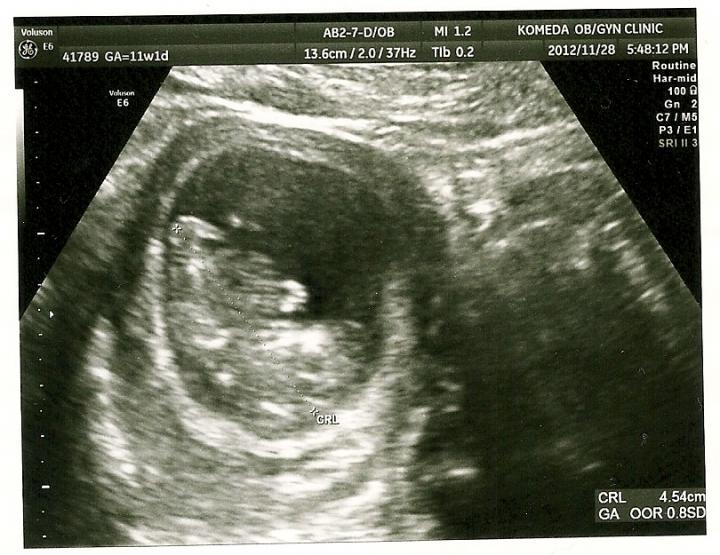

11週1日(^^)

初めて心音ききました(^^)

感動というか、 お~(><)みたいな(笑)